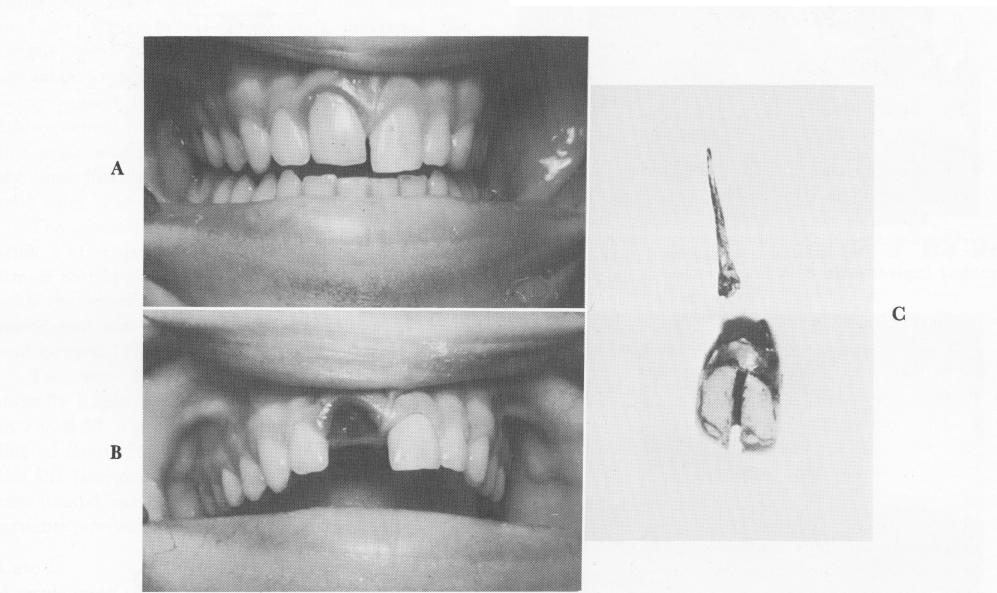

Fig. 8-33. A, The acrylic jacket is seen still held firmly in place 5 years after reimplanting. B, The remaining coronal portion of the tooth was removed with the acrylic jacket and existing gutta-percha point. C, The acrylic jacket is attached to the only remaining coronal portion of the tooth. The gutta-percha point is also seen.